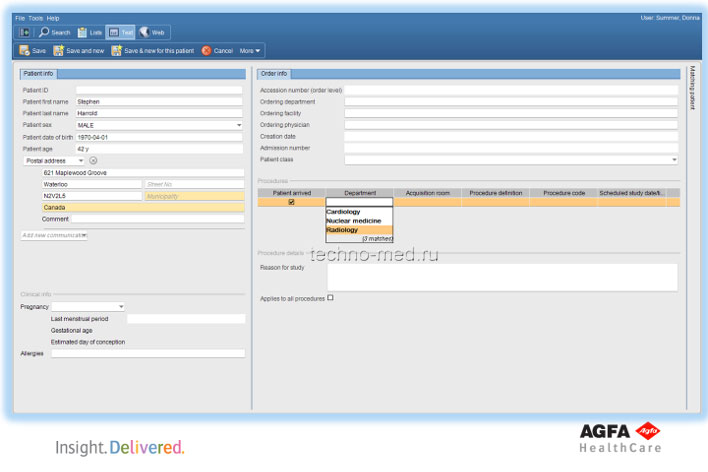

Рабочий стол технолога